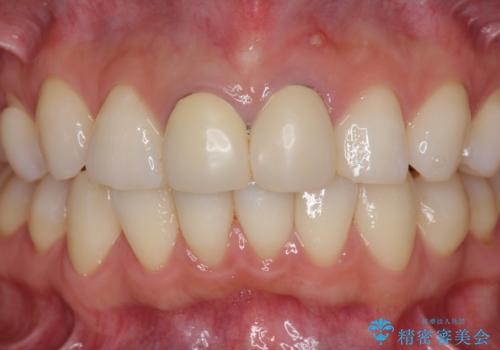

- 26.2万円(仮歯・ファイバーコア・ジルコニアクラウン×2)費用は治療当時の料金となります

今回は根尖性歯周炎に対する根管治療を行ったことで症状は改善し、快適に食事ができる状態へと改善しました。